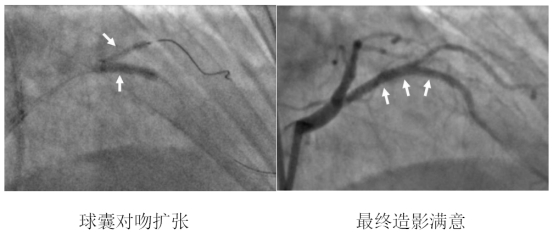

术中,造影结果与术前判断一致,患者前降支血管重度狭窄且病变累及较大分支血管开口,需要介入治疗。公永太教授带领介入团队,凭借精湛的手术技巧,首先分别于前降支及分支送入导丝,在分支预埋球囊保护下,于前降支病变部位置入一枚支架,之后再送入导丝穿支架网眼至分支内,完成球囊后扩张和对吻扩张。操作过程中采用IVUS评估病变、优化支架置入,全程未使用对比剂。整个手术的对比剂用量不足15ml,远远少于一例普通患者单纯造影所用剂量。患者术后复查肌酐无增高,心绞痛症状完全缓解,顺利出院。

IVUS示支架贴壁、膨胀良好